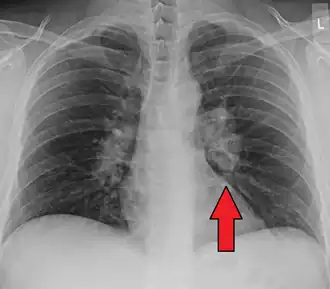

Chest X-ray showing the typical nodularity of sarcoidosis, predominantly in the hila of the lungs.

Chest radiograph changes are divided into four stages:[104]

1. bihilar lymphadenopathy

2. bihilar lymphadenopathy and reticulonodular infiltrates

3. bilateral pulmonary infiltrates

4. fibrocystic sarcoidosis typically with upward hilar retraction, cystic and bullous changes

Although people with stage 1 radiographs tend to have the acute or subacute, reversible form of the disease, those with stages 2 and 3 often have the chronic, progressive disease; these patterns do not represent consecutive "stages" of sarcoidosis. Thus, except for epidemiologic purposes, this categorization is mostly of historic interest.[28]